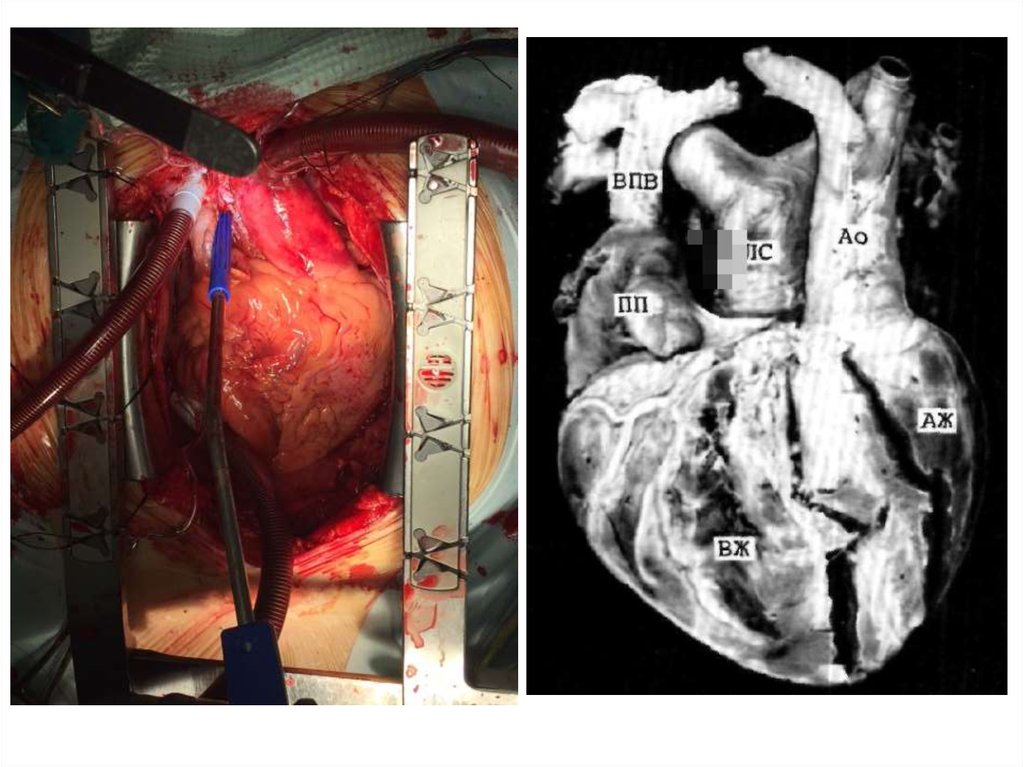

15. Клинический пример 3

• Пациент В., 18 лет находился в КХО ПГКБ с 20.01. по

3.02.15.

• В июле 2014 года при медосмотре перед

поступлением в ВУЗ в г. Санкт-Петербурге был

впервые выслушан шум в сердце. Дообследован в

ФГБУ «ФМИЦ им В.А. Алмазова» МЗРФ, где был

выявлен

ДМПП.

В

сентябре

2014

г,

госпитализировался в АОКБ с целью решения вопроса

об эндоваскулярном закрытии дефекта. Выполнена

СКТ

камер

сердца

с

контрастированием,

подтверждено наличие ДМПП со сбросом слева

направо, связь ЛП с верхней полой веной (ЧАДЛВ) и

впадение левой плечеголовной вены в венечный синус

сердца.

Консультирован

кардиохирургом,

установлены показания к оперативному лечению.

• СКТ-ангиокардиография

(02.12.14.):

Левая

плечеголовная вена впадает в коронарный синус. Правая

верхняя ЛВ впадает в ВПВ. Определяется связь ЛП с ВПВ

(в области верхней ЛВ). Отмечается ДМПП размером 0,5

см.

17.

• Заключительный клинический диагноз:

ВПС: Вторичный ДМПП. Частичный АДЛВ.

Добавочная левая верхняя полая вена. МР I

ст. ТР II ст. ЛГ I ст. Экстраситолия. ФК СН 0-1

(NYHA).

• Операция

(22.01.15.):

Радикальная

коррекция

частичного

аномального

дренажа легочных вен.